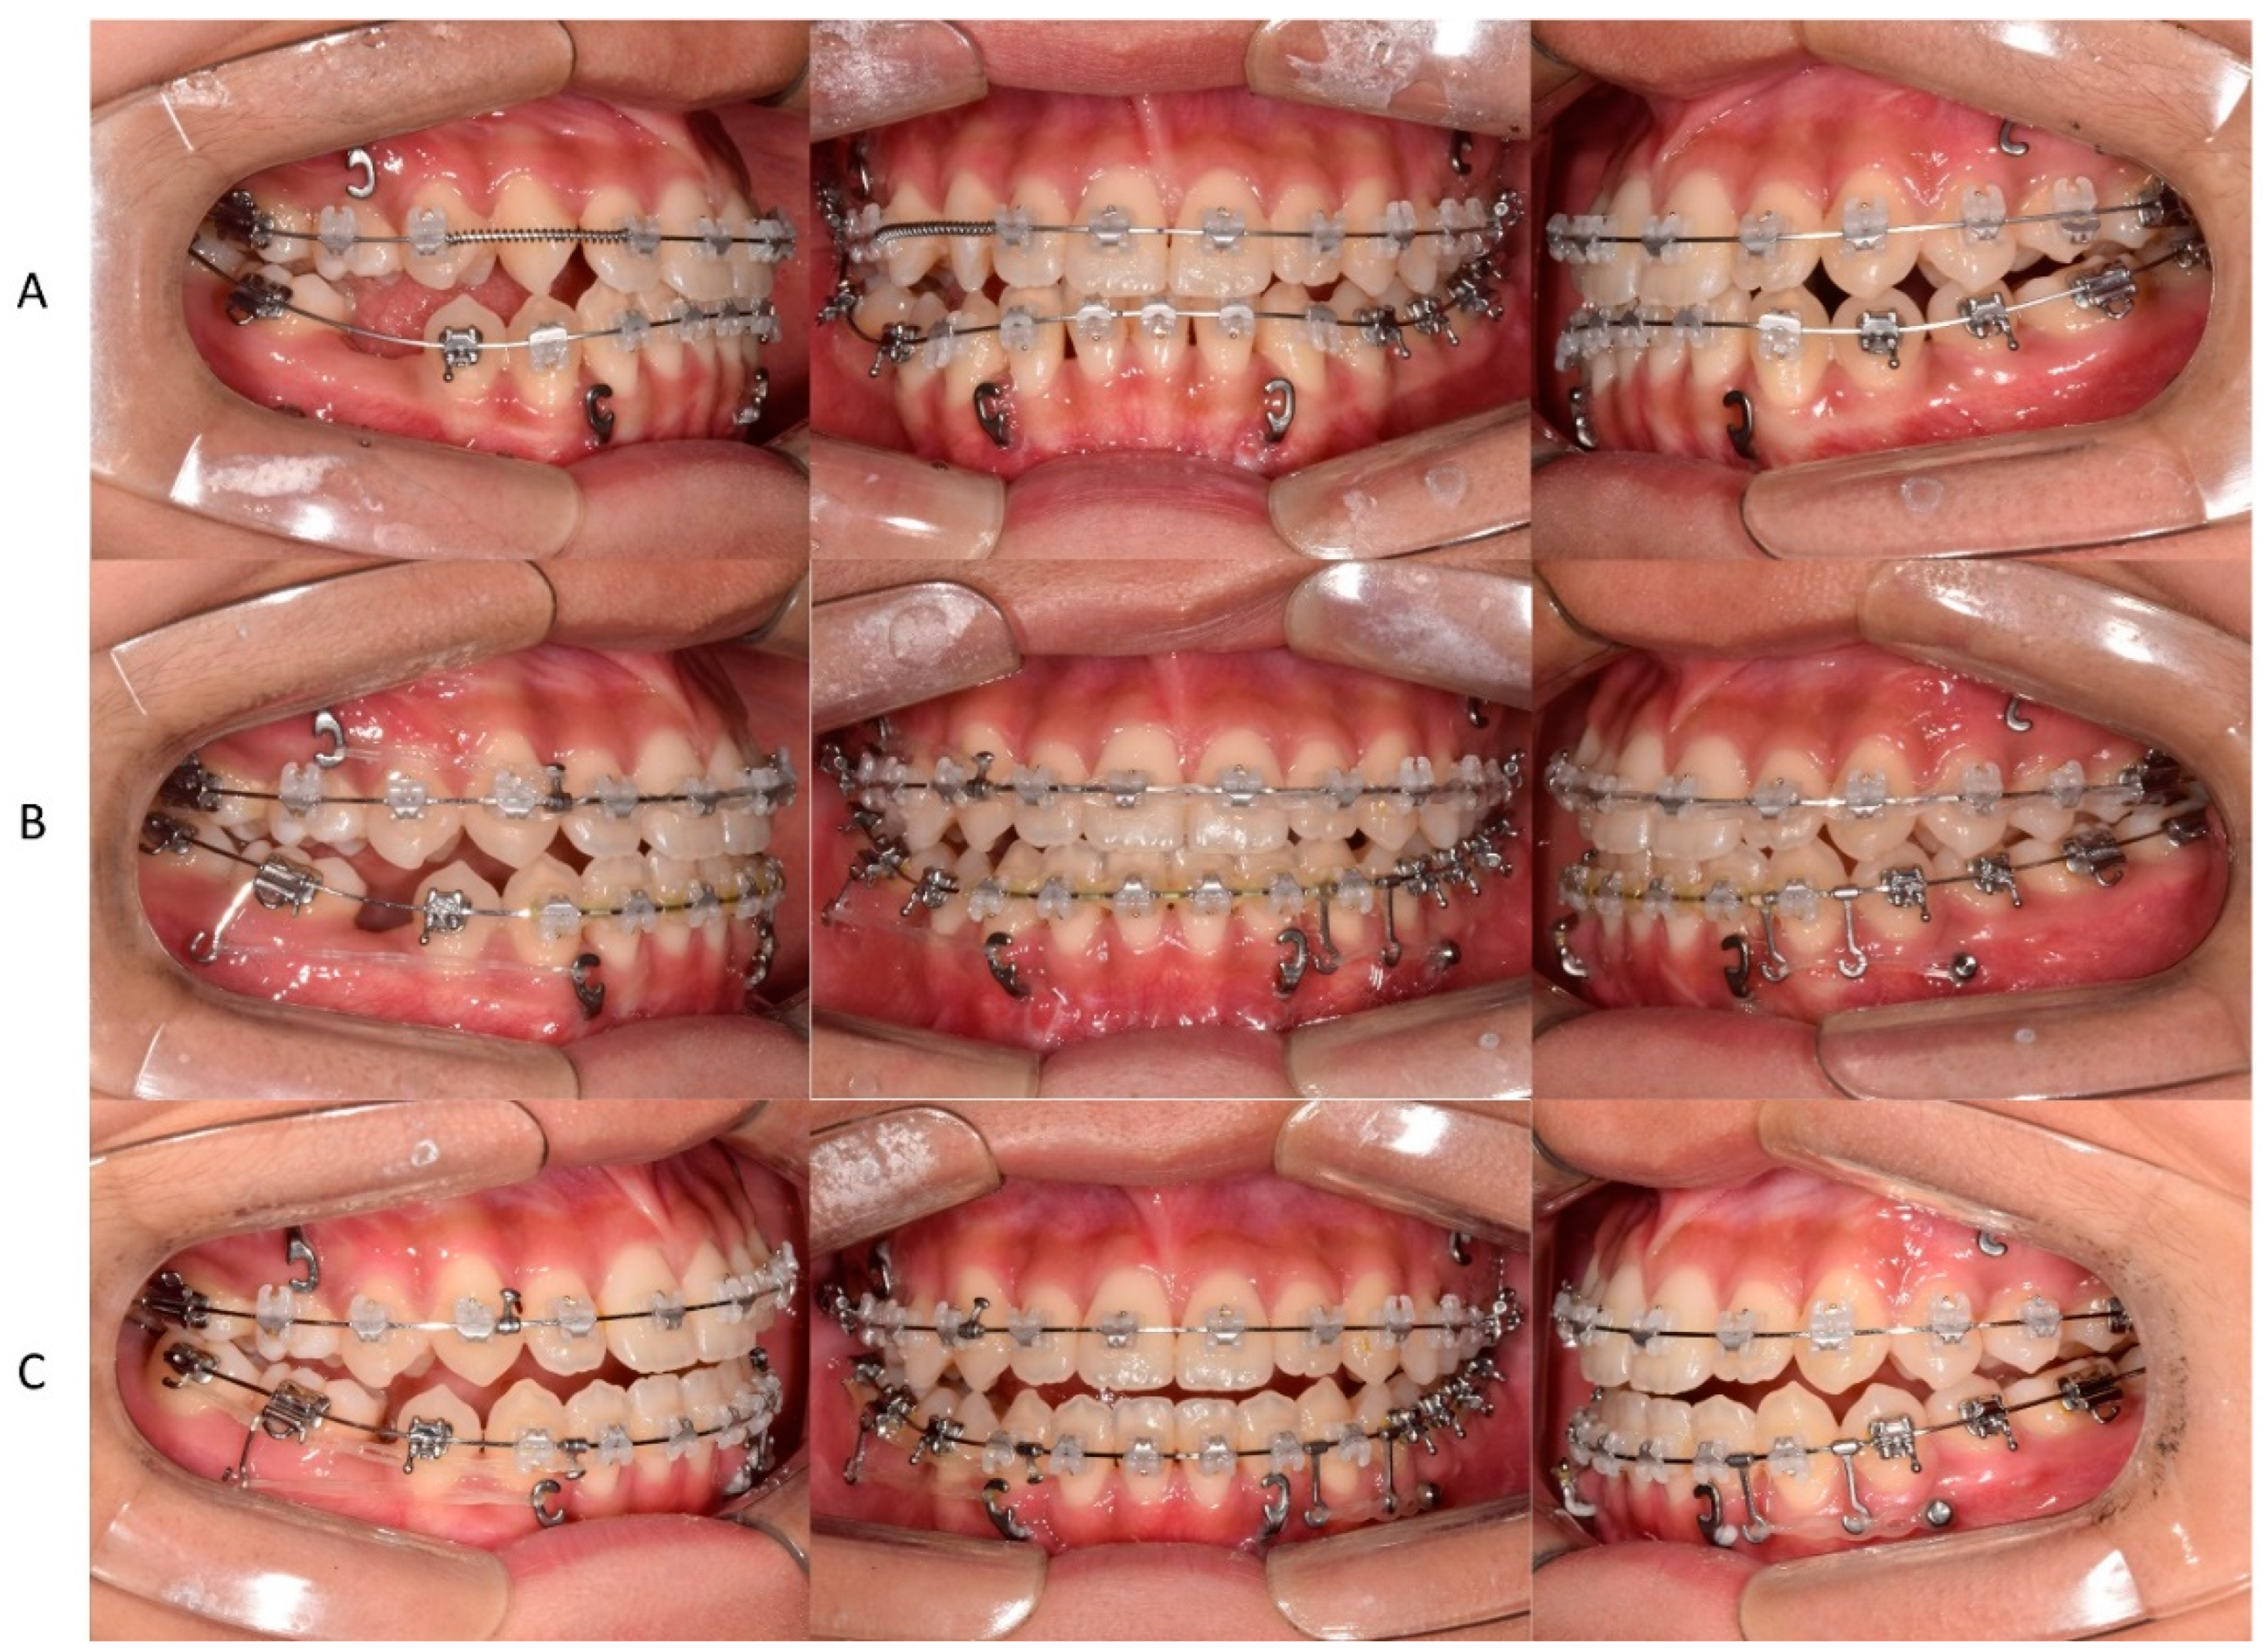

In the second phase, after bonding the fixed appliance to the maxillary and mandibular dentition, treatment started with the following goals: proclining maxillary incisors and closing most of the extraction space of the extracted mandibular primary tooth through protraction of the right molar, which induced spontaneous eruption of the right third molar (Figure 4). In addition, to improve the midline, the mandibular left third molar was extracted, and the mandibular dentition was moved to the left.

An anterior miniplate was used for protraction of the mandibular posterior molars after the extraction of the right primary second molar (Figure 5A). Since the midline of the maxillary dentition was also deviated to the left, total arch distalization was performed towards the right side of the maxillary dentition using the miniplate on the right side of the maxilla to improve the midline. A miniscrew was placed on the left side of the mandible, and distal movement of the dentition was performed to correct the midline and improve the occlusal relationship in the posterior region.

After 39 months of secondary orthodontic treatment, all spaces were closed, the anterior crossbite and lateral open bite improved, and stable occlusion was achieved (Figure 6). After treatment, most cephalometric values, except SNA, improved within the normal range (Figure 7A, Table 1). Panoramic radiography demonstrated that the mandibular right third molar erupted in an upright position (Figure 7B). No significant root resorption was observed in the maxillary anterior teeth, but the periodontal ligament was clearly widened. It was observed that the right maxillary sinus pneumatization was severe up to the place where the impacted tooth was in the past.

Figure 5. Nonsurgical orthodontic treatment process using a fixed appliance. (A) space regaining for maxillary right lateral incisor arrangement after bonding the fixed appliance. (B) Closing the mandibular extraction space using the miniplate anchorage, moving the maxillary midline to the right, and moving the mandibular midline to the left. (C) The mandibular extraction space was closed.